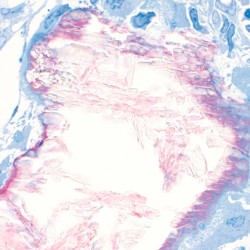

Maxresorb® inject es una pasta ósea sin endurecimiento y lista para el uso compuesta de gel de nano-HA de base acuosa y partículas de Maxresorb®. Debido a su composición específica, las propiedades viscosas de maxresorb® inject permiten una forma, moldeado y ajuste perfectos y una completa adhesión a la superficie ósea circundante del defecto.

Maxresorb® inject es una pasta ósea sin endurecimiento y lista para el uso compuesta de gel de nano-HA de base acuosa y partículas de Maxresorb®. Debido a su composición específica, las propiedades viscosas de maxresorb® inject permiten una forma, moldeado y ajuste perfectos y una completa adhesión a la superficie ósea circundante del defecto.

Biofuncionalidad

Las partículas de nano-HA, ofrecen una superficie muy grande para las interacciones celulares y son rápidamente reabsorbibles.

El componente nano-HA, que representa aproximadamente el 80% del material, se reabsorbe en un plazo de 6-8 semanas.

Los gránulos maxresorb ayudan a mantener el volumen a lo largo del tiempo.

Maxresorb inject es una masilla ósea sin endurecimiento que promueve una rápida regeneración ósea mediante el crecimiento interno de vasos sanguíneos y células a través de su estructura porosa.